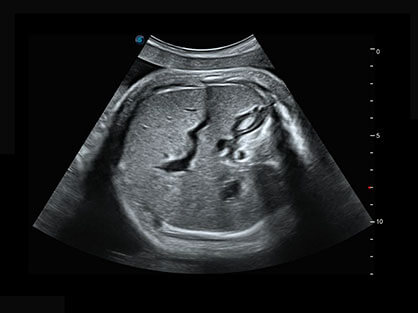

自动获取标准切面,自动完成测量,帮助医生快速完成检查,同时提升测量准确性。